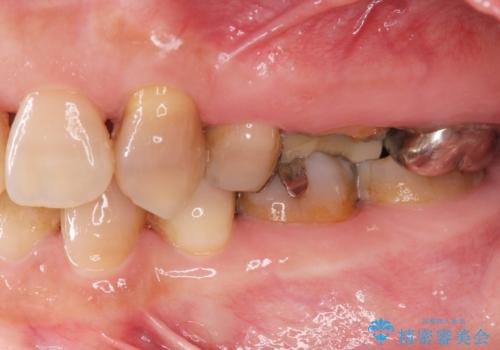

- ぐらぐらする歯や銀歯、なんとなくにおいのする奥歯の治療を求めて来院されました。

X線、歯周組織検査の結果、全体的に奥歯には重度〜中等度の歯周病の問題が見られました。

残すことのできない歯、予後の悪い歯を抜去し、ブリッジイ・ンプラントによる機能回復をおこなっていくと同時に、残すことのできる歯には歯周病治療をしっかりと行い、

将来に渡りしっかりと自分の歯で噛めるような口腔内環境を構築していきます。